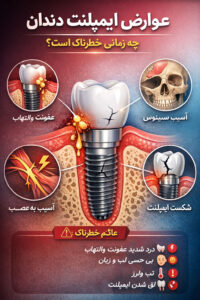

عوارض ایمپلنت دندان

عوارض ایمپلنت دندان: علائم، عوامل خطر و راههای پیشگیری

ایمپلنت دندان یکی از مؤثرترین روشها برای جایگزینی دندانهای از دست رفته محسوب میشود، اما آگاهی از عوارض ایمپلنت دندان اهمیت زیادی دارد. در برخی موارد، مشکلاتی مانند عفونت ایمپلنت یا حتی شکست ایمپلنت ممکن است پس از جراحی یا در بلندمدت ایجاد شوند؛ بهویژه زمانی که مراقبتهای لازم رعایت نشود یا عوامل خطر نادیده گرفته شوند. شناخت این عوارض و توجه به اصول مراقبت بعد از ایمپلنت نقش مهمی در پیشگیری از عوارض پس از جراحی ایمپلنت و افزایش موفقیت درمان دارد.

عوارض جدی و هشداردهنده

اگر علائم بدتر یا ماندگار شدند باید سریعاً به دندانپزشک مراجعه کنید. موارد مهم عبارتند از:

عفونت ایمپلنت (Peri-implantitis): التهاب و ترشح چرکی اطراف پایه ایمپلنت که میتواند به تخریب استخوان منجر شود.

آسیب به اعصاب و بافتها: در مواقعی که ایمپلنت نزدیک عصب قرار میگیرد، ممکن است بیحسی یا سوزش پایدار در لب، چانه یا زبان ایجاد شود.

آسیب سینوسی: در فک بالا احتمال نفوذ به حفره سینوس و عفونت سینوسی وجود دارد.

شکست ایمپلنت: نپیوستن ایمپلنت به استخوان یا عفونتهای پیشرونده میتواند باعث شکست درمان شود.

علائم خطرناک که نیاز به مراجعه فوری دارند

در صورت مشاهده هر یک از موارد زیر فوراً اقدام کنید:

درد شدید و پیشرونده

تب یا ترشح چرکی از محل ایمپلنت

بیحسی یا اختلال حسی پایدار

حرکت یا لق شدن ایمپلنت

خونریزی شدید یا تورم گسترده

بوی بد مداوم دهان